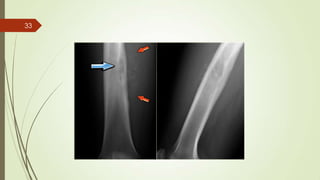

Imaging studies

 X ray : permeative lytic lesion with periosteal reaction.

33